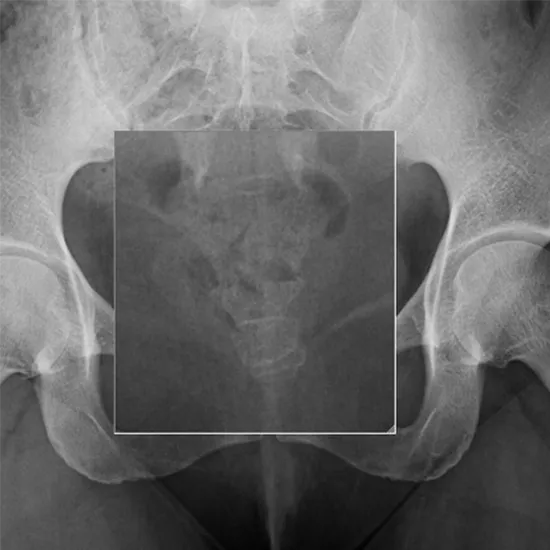

X-Ray Sacrum Coccyx AP View

X-ray The Sacrum and Coccyx (AP View) test demonstrates the most distal portion of the spine in a lateral position. It is utilized alongside the AP projection. It is used to demonstrate the sacrum and coccyx anatomy and determine the reason for coccyx pain. The coccyx (tailbone) is a tiny, triangular bone found at the base of the spine that resembles a shortened tail. It consists of three to five vertebrae.